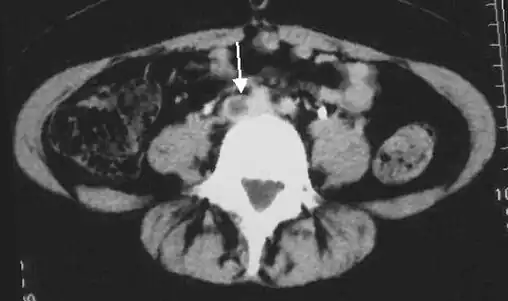

An abdominal CT scan demonstrating an iliofemoral DVT, with the clot in the right common iliac vein of the pelvis

DVT in a leg above the knee is termed proximal DVT (proximal). DVT in a leg below the knee is termed distal DVT (distal), also called calf DVT when affecting the calf,[47][48] and has limited clinical significance compared to proximal DVT.[49] Calf DVT makes up about half of DVTs.[50] Iliofemoral DVT is described as involving either the iliac, or common femoral vein;[51] elsewhere, it has been defined as involving at a minimum the common iliac vein, which is near the top of the pelvis.[19]